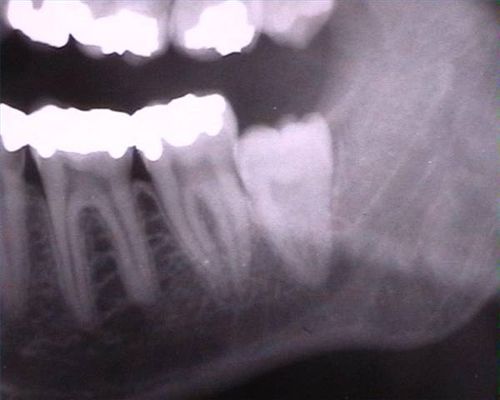

Get your teeth done! I am saying this hypocritically — I have had something crazy going on with some of my molars for a few months now, and I also excuse it with "English teeth". But I doubt that you have anything like the excuse I have, and I'd never heard of this until I experienced it, and if you're going to publish dentistry horror-stories…